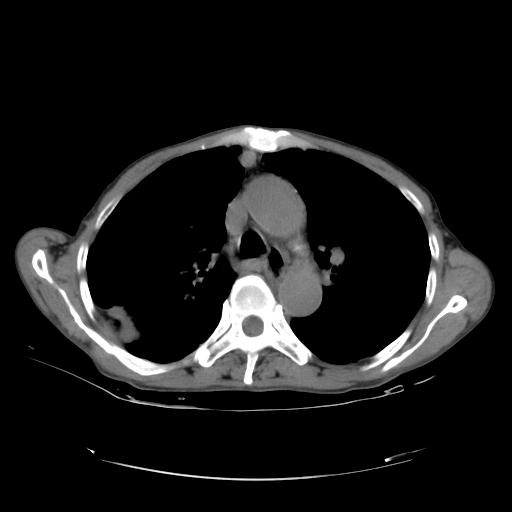

女,72岁,咳嗽一周余,突发右下肢无力二天。

pe:bp-140、80mmhg,精神可,伸舌居中,右上肢肌力正常,右下肢肌力0级,巴氏征+

来院做头颅+胸部ct平扫

遂加作增强:

胸部病变平扫35hu,增强强化至70hu

这个病人首先是胸部病变的定位到底是肺内还是肺外。仔细观察块影位于胸膜下,与胸膜间有透亮带,且近端血管未见明显推移而是引流样改变,形态分叶,说明这个病灶位于肺内胸膜下。很可能是腺癌,腺癌最易致颅内高密度转移灶。局部胸膜有侵犯。

本例颅内见多发大小不等高密度灶,有强化及水肿;另外,胸锁关节层面可能是第四胸椎及右侧肋骨起始部骨质欠连续,椎旁软组织肿胀,建议调骨窗观察。

基于以上原因,所以炎性肿块或胸膜间皮瘤不考虑。

诊断:右下肺癌伴颅内、胸椎、肋骨转移可能性最大。